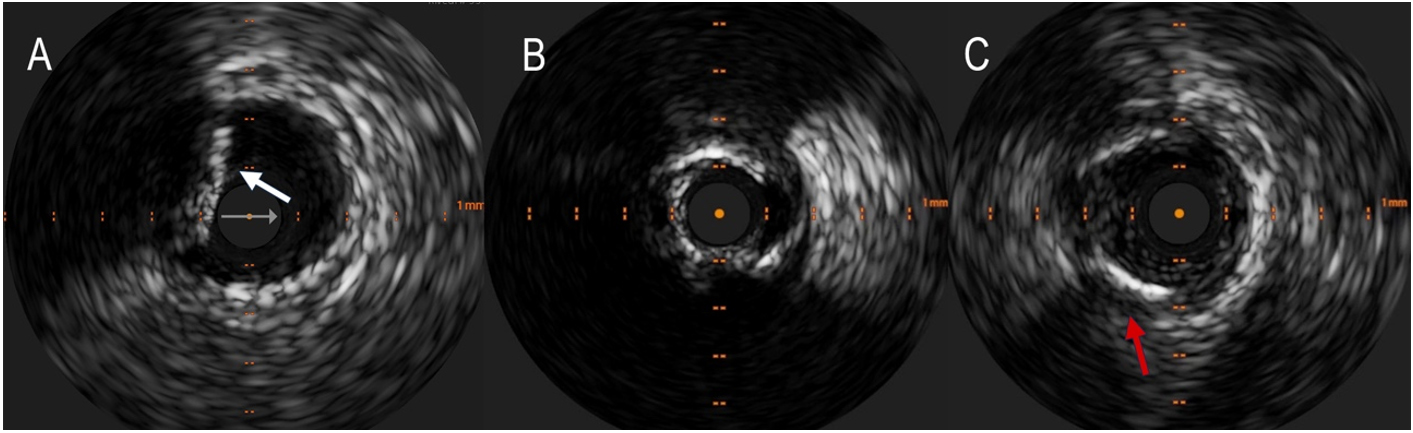

Intravascular Ultrasound (IVUS) is an intravascular imaging technique that can detect calcium as brilliant, hyperechoic lines with acoustic shadowing, discriminating in superficial (close to the lumen) and deep [Figure 3]; thanks to the elevated penetration power of ultrasound, it can see deep calcium, with 150 to

Figure 3. Detection of coronary calcium by IntraVascular ultraSound (IVUS). (A) shows superficial calcium protruding into the vessel lumen (white arrow). A calcium arc > 180° often results in a tight stenosis that can hardly be dilated without appropriate debulking (B). The red arrow in the (C) indicates a deep calcification.

IVUS can semiquantitatively assess calcified plaques, measuring calcium arc and length and estimating the calcific burden. It can also identify calcified nodules (CN) and nodular calcification.

The limitations of IVUS are represented by the inability to detect the thickness of calcium and microcalcifications or if these are placed underneath large necrotic cores; however, calcium usually produces posterior echo reverberations, a very distinctive feature[21,22].

IVUS can guide PCI of CAC from the beginning, with morphologic and semiquantitative calcium assessment, to the end of the procedure, checking the result post-stent implantation. In several prospective and retrospective multi-center trials, IVUS-guided PCI has demonstrated better clinical outcomes than angiography-guided PCI[28], especially for complex PCI[29].

Pre-intervention evaluation is essential to plan the procedure because assessing the calcium subset could guide the plaque modification strategy, the choice for the debulking system, and the correct vessel sizing.

Zhang et al. recently reported an IVUS score for calcified lesions: a superficial calcium arc of > 270° longer than 5 mm, a superficial calcium arc of 360°, the identification of a CN, and a vessel diameter of < 3.5 mm correlated with stent underexpansion[30]; they suggested the use of debulking technique if calcium score is

IVUS could also assess adequate vessel preparation. In this setting, the reverberation phenomenon is frequently observed for severely calcified lesions after rotational atherectomy (RA). It seems to be due to the smooth inner surfaces of calcifications and has been proposed as a surrogate indicator of thinner calcium. Recently, You et al. reported that the number of layers of reverberation signal identified by IVUS is positively associated with the calcifications’ thickness quantified by OCT after RA, and calcium crack after predilatation produces a single layer of reverberation[31].

After stent implantation, IVUS can assess procedural success, measure the stent lumen, check adequate stent expansion, and identify edges dissection and incomplete stent apposition[32].